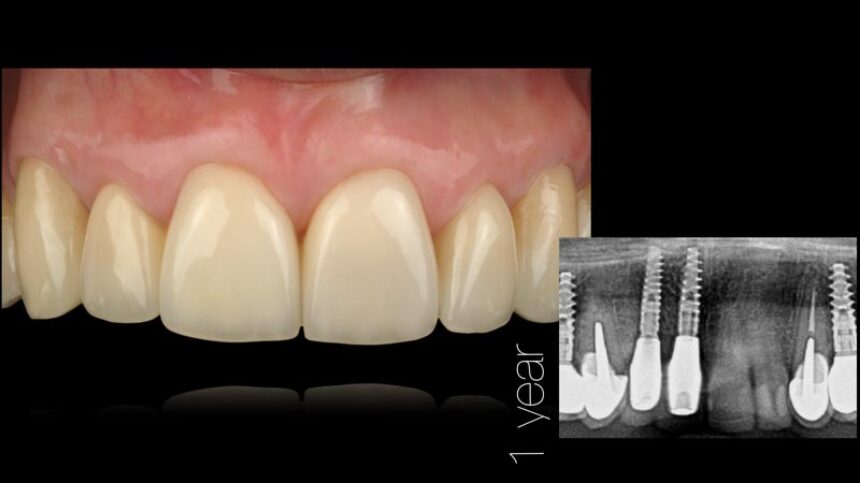

· Η έννοια του σχεδίου θεραπείας με άμεση τοποθέτηση, από την προσθετολογική στη χειρουργική επέμβαση

· βήματα της θεραπείας από την εξαγωγή του δοντιού ως την παράδοση της αποκατάστασης: οι λεπτομέρειες

· κριτήρια που σχετίζονται με τους μαλακούς ιστούς στη θεραπεία με άμεση τοποθέτηση εμφυτεύματος